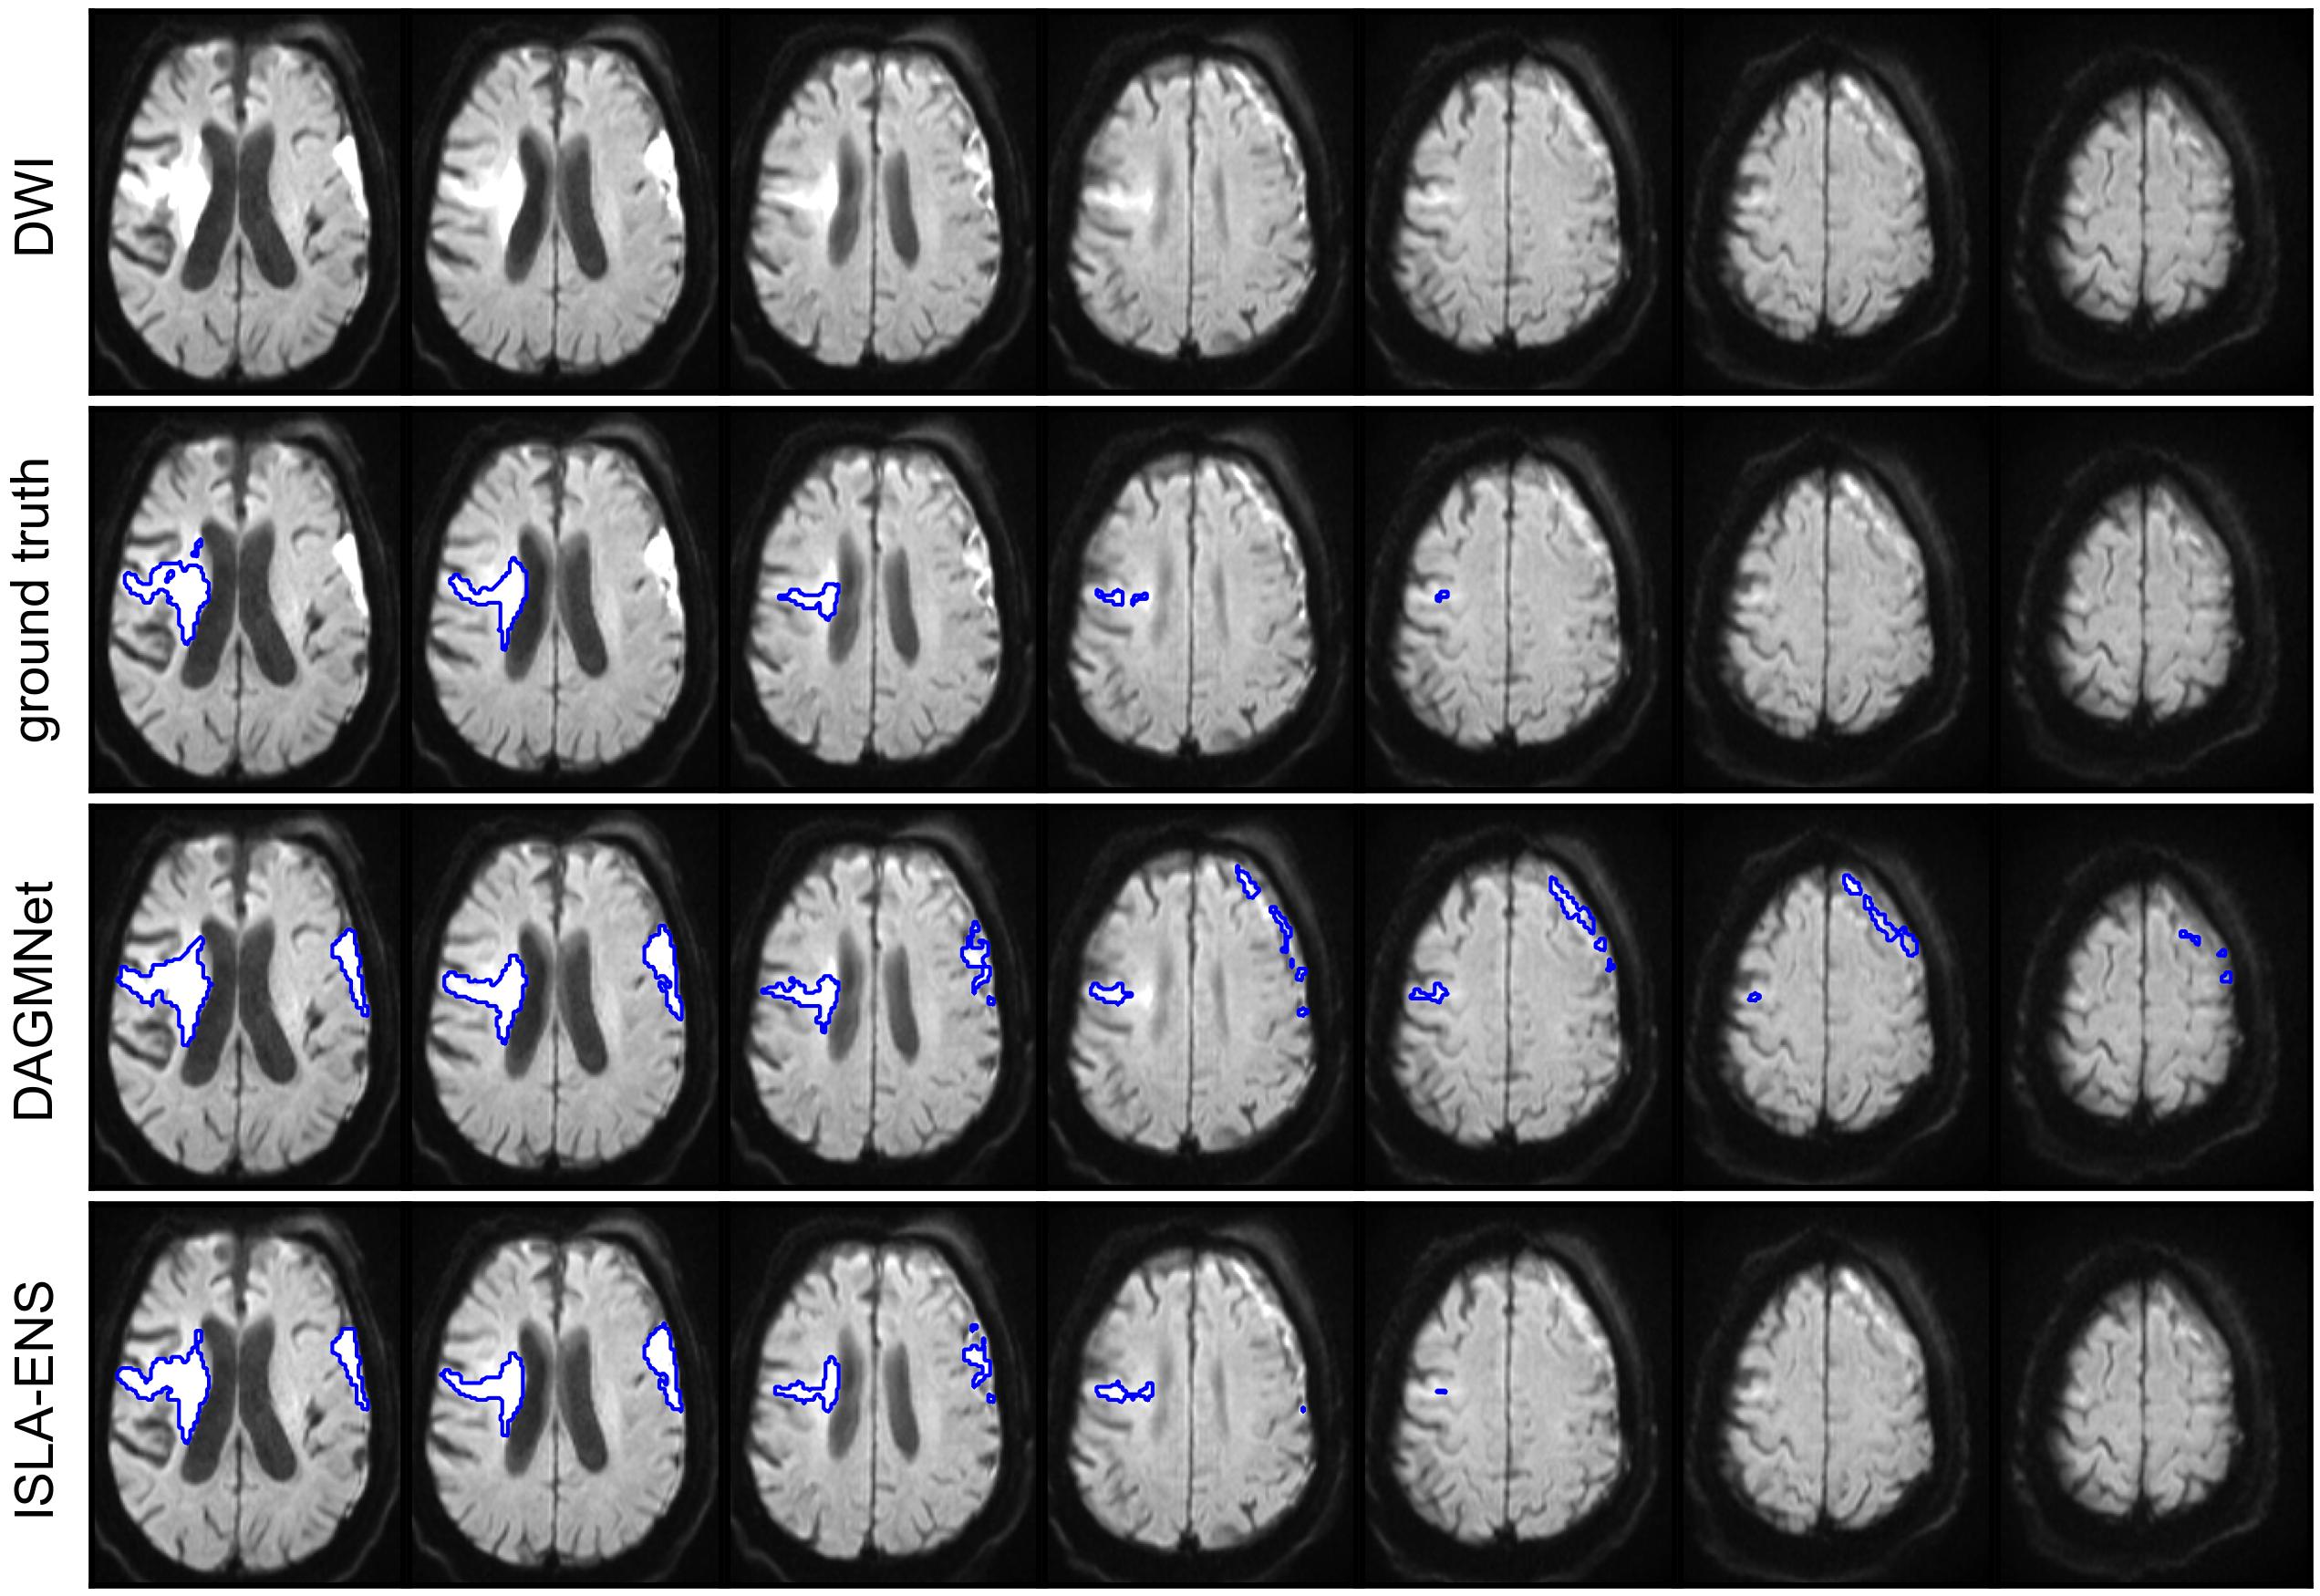

We conducted qualitative comparisons between the best-performing SOTA and ISLA models.

First, within each lesion-size group, we selected for visualization axial slices from the volumes closest to the first, second, and third quartiles of the DSC difference between the two models, excluding cases whose DSC deviated by more than 0.2 from the respective model-specific median within the group.

Figure 4 shows representative examples of segmentations from the test set with DAGMNet and ISLA-ENS, the best SOTA and ISLA models according to the test set case-level ranking (Table 5).

In cases 1 and 2 of Figure 4(a), both models successfully detected the lesions; however, DAGMNet slightly underestimated the lesion extent in case 1. In case 3, a corticospinal tract anisotropy artifact resulted in FPs for DAGMNet.

Cases 1 and 3 of Figure 4(b) further illustrate underestimation of lesion extent by DAGMNet, whereas ISLA-ENS produced segmentations closely matching the manual annotations. In case 2, both models generated FPs due to magnetic-susceptibility artifacts near the nasal region.

In Figure 4(c), case 1 shows accurate delineation of the lesion by both models, with no FPs induced by the inhomogeneity artifact. Case 2 demonstrates a missed small cerebellar lesion by ISLA-ENS. In case 3, both models correctly localized the lesion, but DAGMNet again produced FPs caused by magnetic-susceptibility artifacts around the nose.